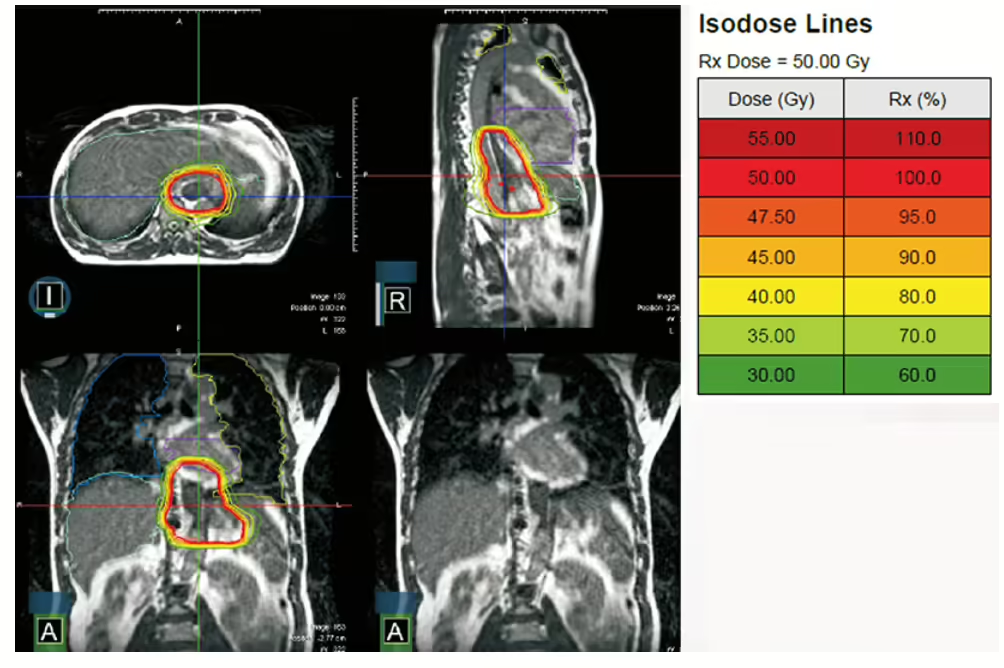

多數病友接受放射治療均是採用外部照射。目前高醫全數採用強度調控放射治療,為期約5-6週,每天一次,一週5次;此種治療能完美包覆腫瘤,讓正常組織劑量降低,但若是要讓腫瘤無所遁形,更建議進一步搭配「精準影像導引對位」,透視身體,掌握腫瘤位置;而對於最會移動的食道末端及胃食道交接處腫瘤,還能再搭配「呼吸調控技術」來追蹤腫瘤,克服呼吸導致的位移。藉由輔助技術的搭配,除了帶來精準度提高的優勢,對於壓迫症狀嚴重的腫瘤,還能針對腫瘤的地方提高劑量,實現個人化醫療。

圖說:放射治療搭配核磁共振影像導引 (MRI)技術,及輔助呼吸調控,克服最會移動的下段食道位移,治療更精準。